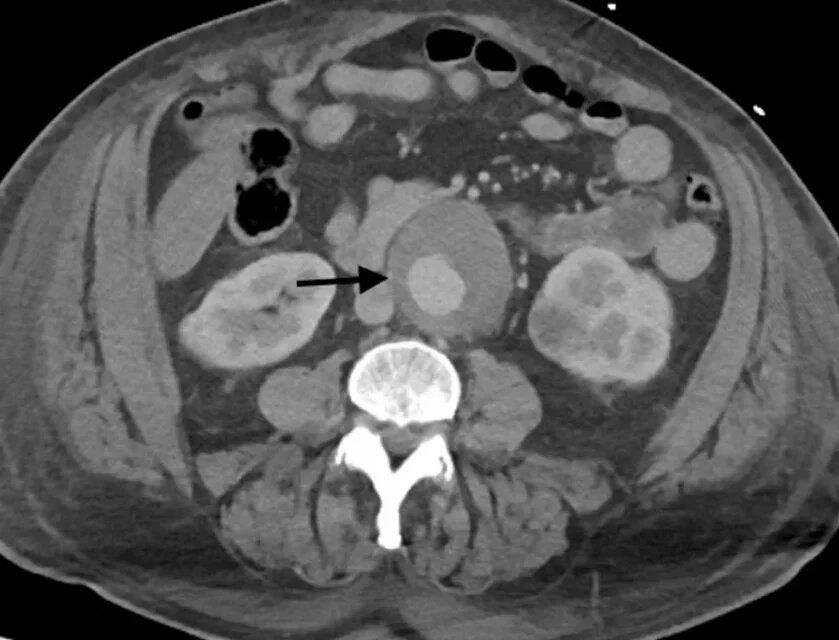

68-летний мужчина обратился в отделение неотложной помощи с жалобами на боль и припухлость в мошонке и правом паху, возникшие после приступа повторяющегося кашля. Врачи обнаружили у него спонтанный разрыв яичка, вызвавший разрастающуюся гематому.

Также пациент страдал сердечной недостаточностью. В течение трех месяцев его мучил изнурительный кашель, появились отеки нижних конечностей, одышка и боли в груди. Отек распространился на живот, на паховой области и на бедрах образовались синяки, а на мошонке - большая гематома. Яичко не поддавалось восстановлению, и для устранения кровоизлияния потребовалась орхиэктомия.

Специалисты провели патологоанатомическое исследование удаленного яичка, которое не выявило никакого заболевания, объясняющее этиологию разрыва. То есть мужчина действительно получил тяжелую внутреннюю травму из-за кашля.